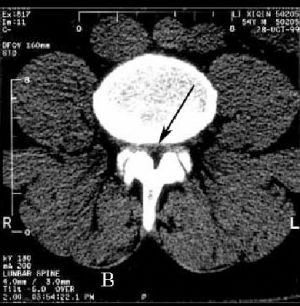

Стенозом позвоночного канала называют уменьшение его размера в передне-заднем направлении, а также уменьшение его ширины. Сужение позвоночного канала в поясничном отделе наиболее часто встречается при гипертрофии (увеличении) фасеточных суставов, желтой связки, уменьшении фораминального отверстия (места выхода нервного корешка из позвоночного канала) за счет разрастания остеофитов, изменении оси позвоночника (сколиоз, спондилолистез). (Рис.1,2А,В)